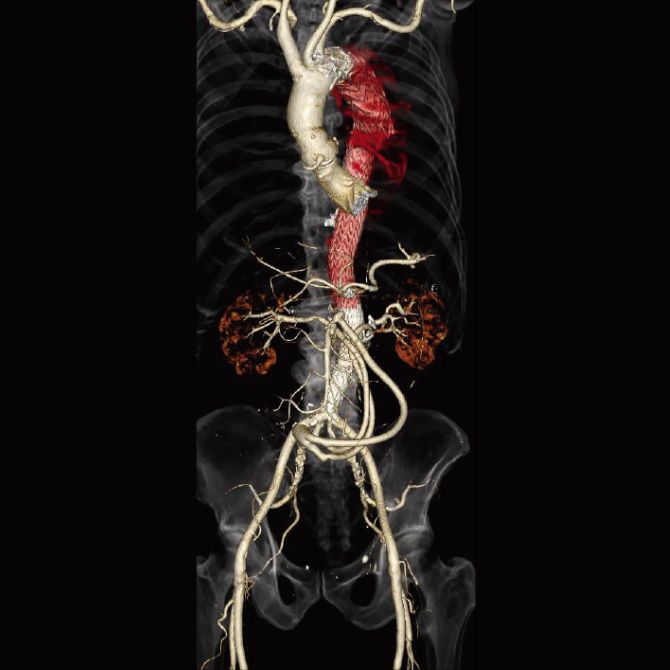

大動脈瘤は、偶発的に診断されることが多いですが、一定のサイズを超えると破裂する可能性があり、破裂をきたした場合の死亡率は80%以上とされ、破裂前の治療が大事になります。治療法は、人工血管置換術とステントグラフト内挿術があります。

併存疾患や年齢により人工血管置換術に耐えれない方に向けて、体への負担が少ない治療が開発されました。

足の付け根の血管から、カテーテルを使用して人工血管(ステントグラフト)を大動脈に挿入し、大動脈瘤破裂を防ぐ治療になります。

当院では皮膚を切開しないで行うステントグラフト治療を積極的に施行しております。他施設に先駆けて2013年から皮膚を切開しないでステントグラフト治療を行い、胸部大動脈瘤でも導入しております。導入から500例を超える症例に皮膚を切開しないステントグラフト治療を行いましたが、入院日数は平均3-6日です。局所麻酔で行うため、全身麻酔が困難といわれた方に対しても安全に治療をしています。

腹部大動脈瘤破裂に対して施行した緊急ステントグラフト内挿術

当院では豊富な経験により多くの方に治療を施行しております。特にハイブリッド治療と呼ばれる「血管バイパス手術とステントグラフト治療」を組み合わせた治療があり、体への負担を最小限に抑えた方法です。他院で治療が困難といわれた大動脈瘤・大動脈解離の方も、お気軽にご相談下さい。